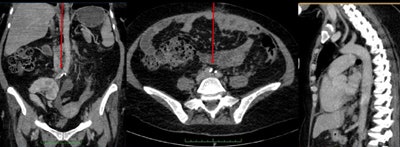

The study team scanned 178 consecutive modern Egyptian patients, all of whom had been referred by their primary physicians for cancer staging with PET at the Alfa Scan Outpatient Radiology center in Cairo. All patients were scanned on a Gemini TF PET/CT scanner (Philips Healthcare) in a single session from the base of the skull to the knee. Images were acquired using 1-mm slices and an average time interval of 0.8 msec. Interpretation consisted of searching for vascular calcifications in different vascular beds.

In both ancient and modern populations, "vascular calcification starts at the peripheral vascular bed (iliofemoral then aortic beds), then spreads to the target vessels (coronary and carotid beds) around a decade later than the onset of aortoiliac calcification," the authors wrote. There was also a trend toward higher incidence of vascular calcification among female mummies, but not modern Egyptians. Allam and colleagues hypothesized that the women may have been exposed to household smoke.

In a previous analysis of large numbers of modern patients (the Multi-Ethnic Study of Atherosclerosis, or MESA), abdominal aortic calcification was shown to be strongly associated with subclinical cardiovascular disease in other vascular beds, including the coronary, carotid, and leg arteries, the authors noted. This led investigators to conclude that the high prevalence of abdominal aortic calcification, even when coronary or carotid disease was not present, might suggest that atherosclerosis began earlier in the abdominal aorta compared to event-related vascular beds such as the coronary arteries.

And if disease begins in the abdomen before it reaches the coronaries, maybe that's where screening should start, according to Allam. "Occurrence of aortoiliac calcification a few years earlier than the coronary arteries could be used as an important screening tool for effective preventive cardiology strategies," he wrote in his email.